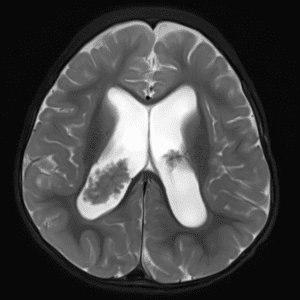

Case #14

CNS toxoplasmosis